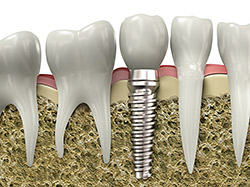

implantsDental implants are a wonderful way to replace missing teeth and to preserve other teeth. A dental implant is made of medical grade titanium and is designed to replace the root of a missing tooth. The implant integrates with the jawbone, anchoring it securely and allowing a crown, bridge or denture to be placed on it by your restorative dentist. This results in improved function and comfort. If a tooth must be removed, in some circumstances the dental implant can be placed at the time of extraction. Other times the extraction site must be rebuilt with a bone graft in order to establish a firm foundation. We are proud to use the most up to date techniques and technology to restore missing teeth with esthetic comfortable implants. To find out if you are a candidate for an implant, call the office for an evaluation.

Dental implants are titanium anchors used to permanently replace teeth that are missing, cannot, or should not be saved. Dental implants themselves serve as tooth root replacements to support caps, bridges, or dentures. Developed in the 1960’s, modern dental implants revolutionized dentistry and have become the standard of care for replacement of missing or soon to be missing teeth. Dr. Patino has vast experience in the placement of dental implants.